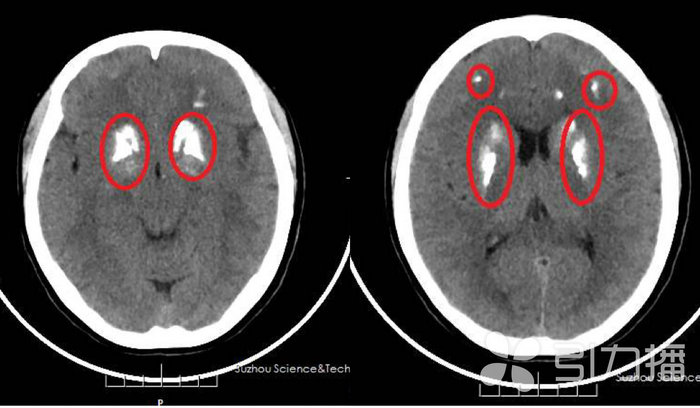

据了解,现年31岁的周女士常常出现头晕头胀的情况,情绪烦躁容易生气,夜间睡眠也不好,日前到苏州科技城医院就诊。该院神经内科主治医师李瑞霞建议周女士做CT检查,这一查发现,周女士的两侧大脑及小脑的多处出现对称性钙化影(如图所示)。于是李瑞霞建议她立即办理住院进行系统检查。

蔡增林介绍,根据患者的症状、检查结果以及基因检测结果,该患者诊断为“特发性基底核钙化”,又称“Fahr病”。该病是以脑部双侧基底节对称性钙质沉着为病理学特征的一组疾病,常有家族遗传性,早期可表现为头晕、头痛,逐渐发展为认知功能障碍、运动障碍、不自主运动、肌张力增高、癫痫发作等症状。